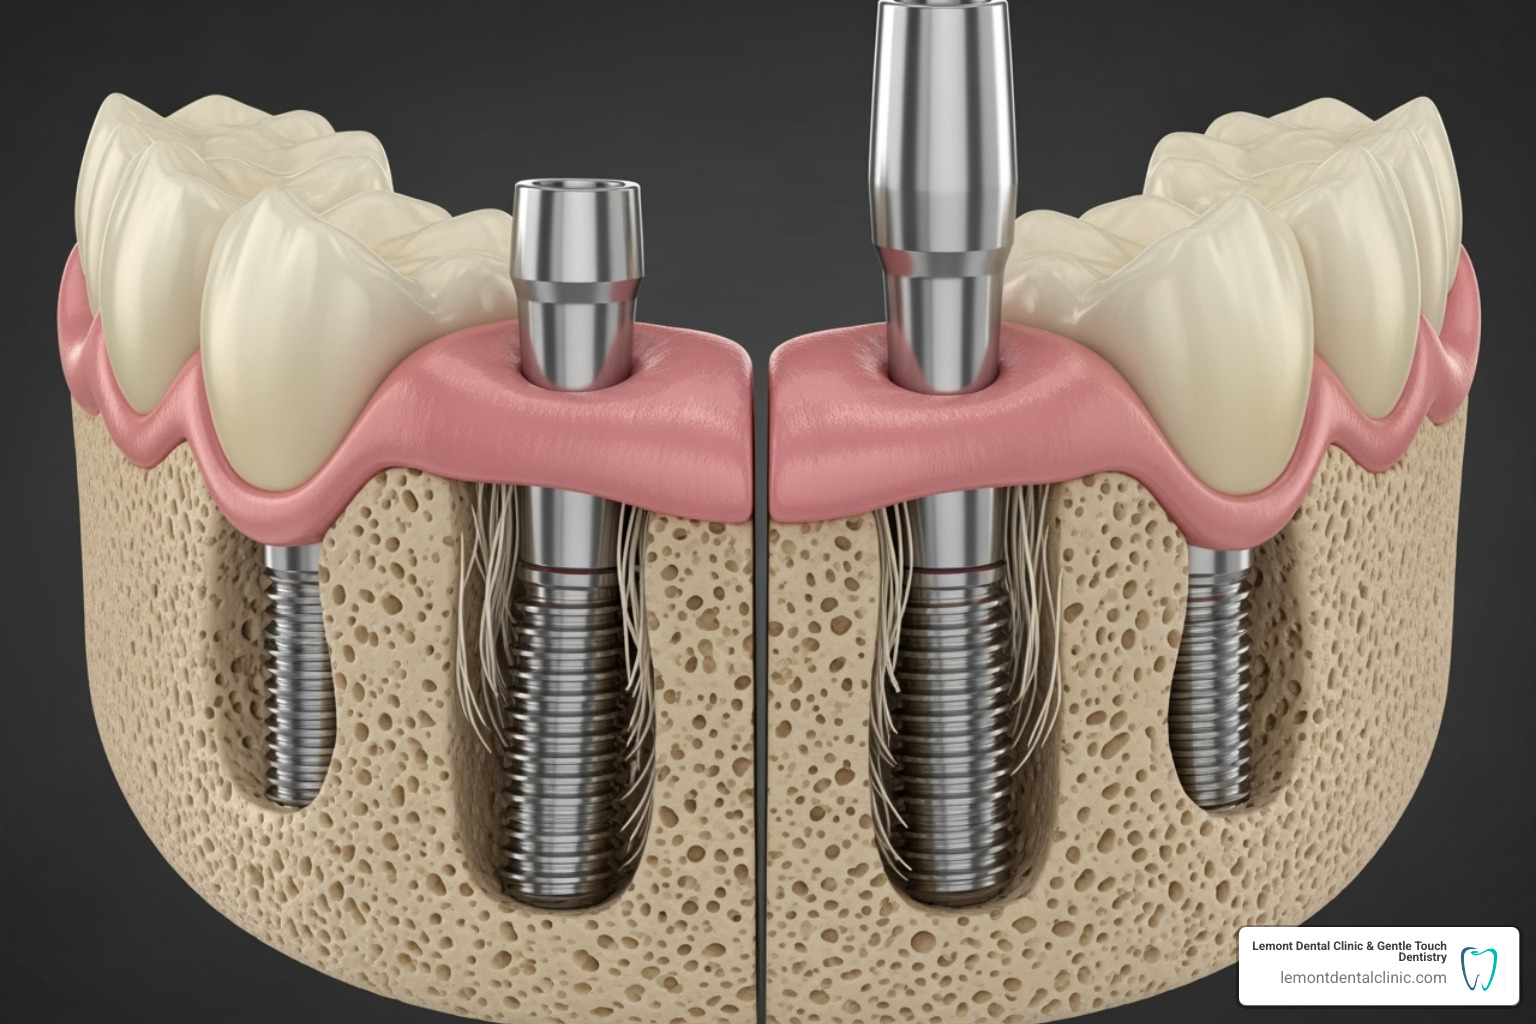

Dental implants are small titanium posts surgically placed into your jawbone. Over a few months, your jawbone fuses with these posts in a process called osseointegration. This creates a strong, stable foundation, much like natural tooth roots.

Once the implants are integrated, your custom denture is designed to snap onto them. This unique connection provides incredible stability, allowing you to eat and speak without worry. The American Dental Association (ADA) highlights how these dentures are held firmly by implanted posts, not just gums. You can learn more on the ADA’s website.

Implant placement is a routine procedure performed by a specialist. After applying local anesthesia for your comfort, the surgeon places the titanium implant posts into the predetermined sites in your jawbone. If needed, bone grafting can often be done at the same time. The procedure typically takes a few hours. According to The American Academy of Periodontology, the entire process can take up to six months, especially if bone grafting is required.

Step 3: Healing and Osseointegration

This crucial healing period lasts 2 to 6 months. During this time, your jawbone fuses with the titanium implants in a process called osseointegration, creating a rock-solid foundation. We will provide you with temporary dentures so you can eat and speak comfortably while you heal. Following our post-surgery care instructions is essential for a successful outcome.

Step 4: Attaching and Fitting Your Final Denture

Once osseointegration is complete, we move to the final stage. First, we attach connectors called abutments to the top of your implants. These are the parts your denture will snap onto. We then take precise impressions of your mouth and abutments, which our lab uses to craft your custom denture.